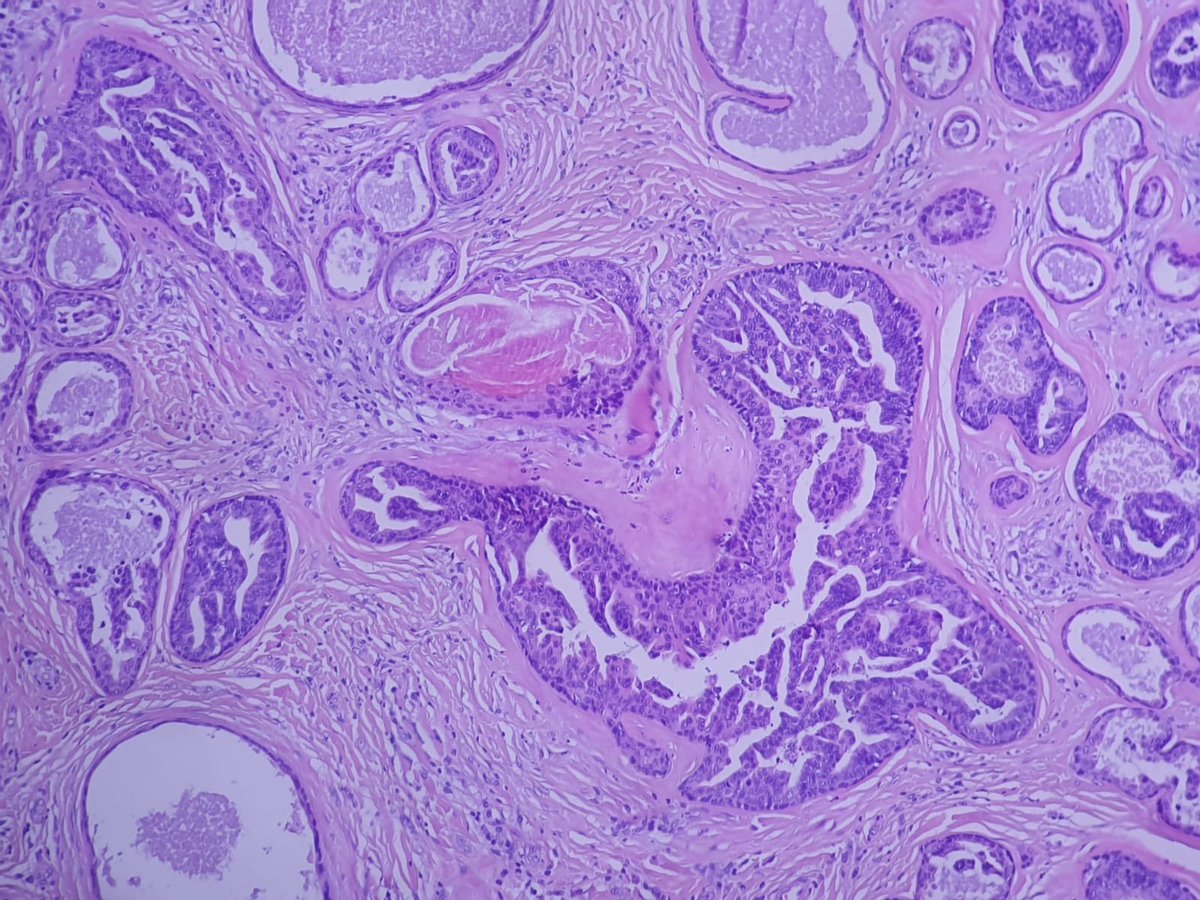

ISGyP 162.7: 71 yr female: Ovarian tumour: Diagnosis: Mesonephric-like adenocarcinoma. Ovarian MLA is an extremely rare neoplasm that has been reported in women between the ages of 50 to 73. The differential diagnosis of such a neoplasm includes FATWO, Mets etc

Ovarian MLA is an extremely rare neoplasm that has been reported in women between the ages of 50 to 73. The differential diagnosis of such a neoplasm includes FATWO, Mets etc